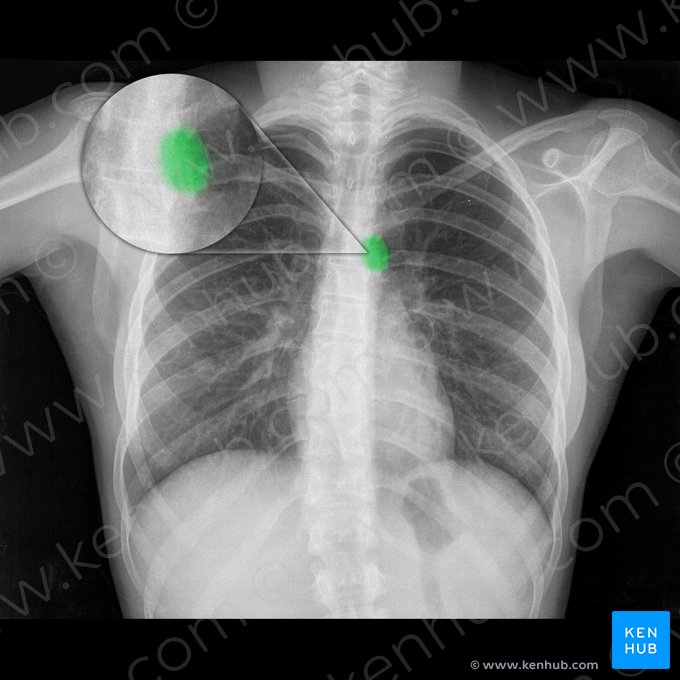

Eine Röntgenaufnahme des Brustkorbs (auch Röntgen-Thorax genannt) ist ein häufig genutztes bildgebendes Verfahren. Es kann aus verschiedenen Perspektiven aufgenommen werden: postero-anteriore Projektion (p.a.), antero-posteriore Projektion (a.p.), linke und rechte laterale Projektion (l.l., r.l.). P.a. und a.p. werden am häufigsten verwendet, während seitliche Projektionen zur Befundung der Wirbelsäule genutzt werden und um zu beurteilen, wie nah sich eine Struktur an der Brustwand befindet. Bei der Überprüfung eines Röntgenbildes müssen wir zunächst die Bildqualität mit folgendem Schema bestimmen: Rotation (Schlüsselbeine und Wirbelsäule in gleichem Abstand), Inspiration (mindestens 9 Rippenpaare sollten zu sehen sein), Projektion (handelt es sich um eine a.p-, p,a,-, l.l- oder r.l.-Aufnahme) und Belichtung (Lungenspitzen, Rippenwinkel und Brustwirbel sollten alle zu sehen sein).

Dann können wir zur Beurteilung des Bildes übergehen. Am einfachsten lässt sich eine Röntgenaufnahme des Brustkorbs nach der ABCDE-Regel auswerten, die für Airway (Atemwege), Breathing (Beatmung), Cardiac (Herz), Diaphragm (Zwerchfell) und Everything else (alles andere wie Knochen, Weichteile, Brust) steht.

Wenden wir nun diese Techniken an, um die folgenden Röntgenbilder des Thorax auszuwerten und das normale anatomische Erscheinungsbild des Brustkorbs zu beurteilen.